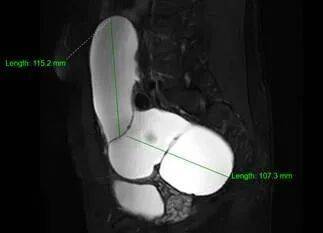

2. 影像学进一步检查:若超声无法明确,可做盆腔CT或MRI。CT/MRI能更清晰地显示假囊的位置、大小、与周围器官的关系,排除恶性病变(如卵巢癌、转移性肿瘤等)。